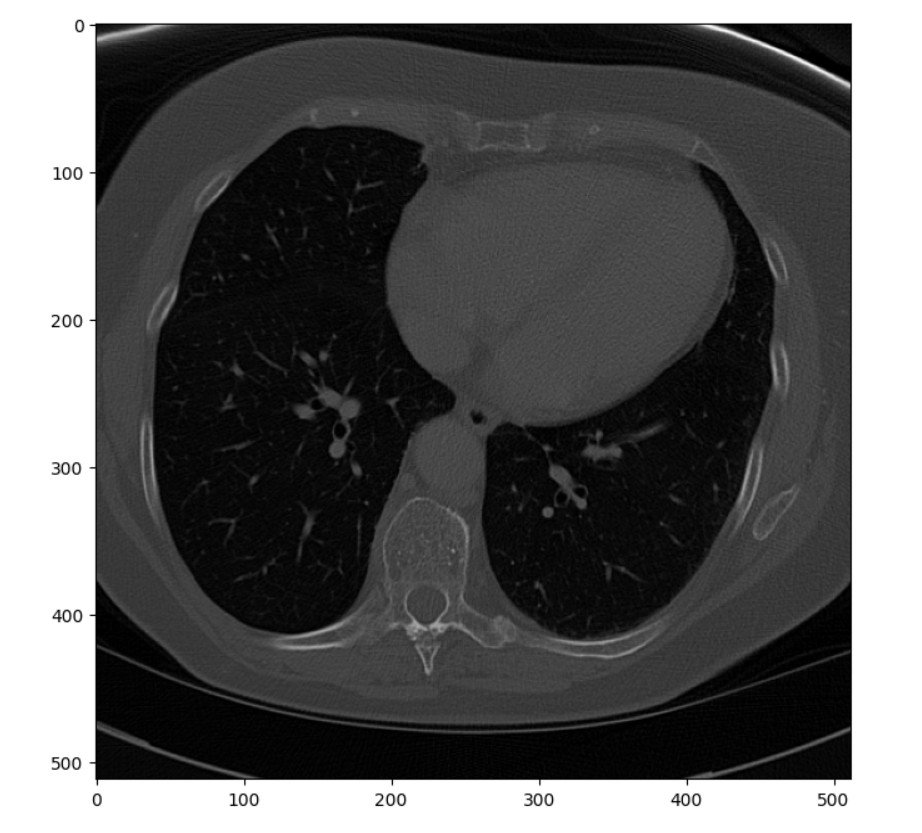

Single Image

The code listing below pulls a single slice from the middle of the stack and renders it as a matplotlib

figure.

# Show one sample image from the archive plt.pyplot.figure(figsize=(8, 8), dpi=100) plt.pyplot.imshow(ct_idata[15,:,:], cmap=plt.cm.gray) # The coloring of the image is controlled by the plt.cm.gray. # While color levels can be useful to visualize specific parts # of an image, using gray helps with inspection in this type # of a processing workflow.

Image Series

The single image represents a pretty standard, unprocessed scan. It was selected more or less at random from the stack and happens to come from about mid-level in the chest. While completely adequate, it could be enhanced before being passed to a radiologist for reading or to a machine learning algorithm for segmentation. One common enhancement is to improve the contrast between different tissue types, such as bone and muscle. While some distinction between the tissues is visible in this image, it is subtle.